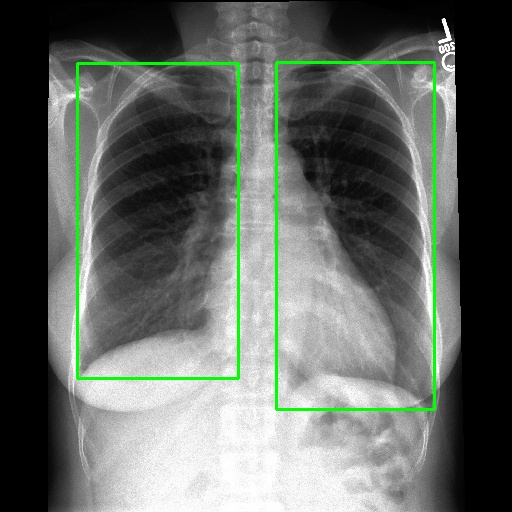

We employ various strategies to locate Regions of Interest (ROIs) in images. For datasets that already include localization annotations, such as segmentation masks or bounding boxes, we derive the ROIs from these existing annotations. Specifically, bounding boxes are directly used as the ROIs, while segmentation masks are converted to ROIs by creating the smallest bounding box that covers the mask. When such localization annotations are not available, we apply different pretrained expert models listed in the Appendix to generate ROIs. For text-prompt driven grounding model[29], we use disease and organ information in coarse captions as text prompts to guide the model in segmenting specific parts. Examples of generated ROIs from various modalities with different models are demonstrated in Figure 6. It is important to note that for modalities such as X-ray and MRI scans viewed from the z-axis, our ROI localization employs a coordinate system relative to the human body, resulting in a left-right reversal in the image representation.

Without ROIs, the original description is limited to a brief global analysis of the image. However, with ROIs, MLLMs  can perform a more detailed local analysis of the ROIs and assess the impact of lesion ROIs on the surrounding normal regions, as demonstrated in Figure 4.

(a) Example of locating ROI via SAT[29].

(b) Example of locating ROI via BA-Transformer [30].

(c) Example of locating ROI via Chexmask [31].

Figure 6: Example of ROIs and their corresponding textual descriptions.